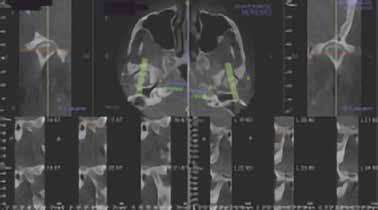

A páciens 3D CBCT lágy szövet renderelése. Szagittális CBCT-felvétel a csontszövetekről és a légutakról.

1. ábra: Nyelv helyzete az okkluzális sík felett.

2. ábra: Mallampati besorolás 4, mindegyik minimális orális térfogatot jelez.

3. ábra: Porckorongmozgás, perforációk nélkül, gyulladással összhangban. A függőleges szaggatott vonal elválasztja a lágy szöveti rezgéseket (0–300 Hz) a kemény szöveti rezgésektől (>300 Hz).

angiotenzin II receptor antagonista) 50 mg naponta egyszer, Nexium (protonpumpa-gátló, amely csökkenti a gyomorban termelődő sav mennyiségét) (GERD) 40 mg naponta, Intuniv (multivitamin) 4 mg naponta, és aszpirin 81 mg naponta egyszer. Klinikailag a nyelv az okkluzális sík fölött helyezkedett el, hiperkeratózis (B), a nyelv légutakba való behúzódása és Mallampati 4, amely mind minimális szájüregi térfogatra utalt (1–2. ábra). Ezek indikálták az alvásfogászati készülékes kezelést. Az izomtapintás elhanyagolható volt, és az állkapocs mozgástartománya is normális volt. A maximális nyitás 45 mm volt (1–2. ábra), oldalirányú elmozdulással 12, illetve 10 mm balra és jobbra. Az állkapocs normál mozgástartománya 42–52 mm volt maximális nyitás esetén, emellett oldalirányú elmozdulás 14 mm volt [13]. Az állkapocs ízületeinek dinamikus funkcióértékelését Joint Vibration Analysis (JVA [BioResearch]) segítségével végezték, és a lágy szövetek esetében a normál határokon belülinek, valamint kétoldali porckorongok perforációjának mentesnek találták (3. ábra)

Az ízületek háromdimenziós képalkotása a condylusok és a fossa osteogenetikus átalakulását mutatta ki, amely az ízületek hosszú távú terhelésére utal (4–5. ábra)

A hipertrófiás gonialis szögek a felszíni masseter izmok kétoldali gyakori és folyamatos összehúzódásainak következményei, amelyek fokozott hypercapneával járnak együtt (megnő a CO a vérben) [14-15]. A hypercapnoe az OSAban a légzésre való ingerlés. A páciens gonialis szögének hipertrófiája jól látható volt a felvételen (6. ábra). Az okkluzális analízis II. osztályú volt, bruxizmusból eredő attrícióval. Standard fényképfelvételeket is készítettek (7. ábra). A páciensnél egy szakképesítéssel rendelkező alvásszakértő orvos poliszomnográfiát (PSG) alkalmazva súlyos OSA-t diagnosztizált. Apnoe/ hypopnoe-indexe (AHI) 79,9 volt (az AHI 30

4. ábra: A CBCT-vizsgálat 3 dimenziós információkat nyújtott a kondilusokról.

5. ábra: Az ízületek 3 dimenziós képalkotása a kondilusok és a fossa oszteogén átalakulását mutatja, amely az ízületek hosszú távú terhelésére utal.

6. ábra: A felvétel a páciens jobb és bal oldali gócszög hipertrófiáját mutatja.